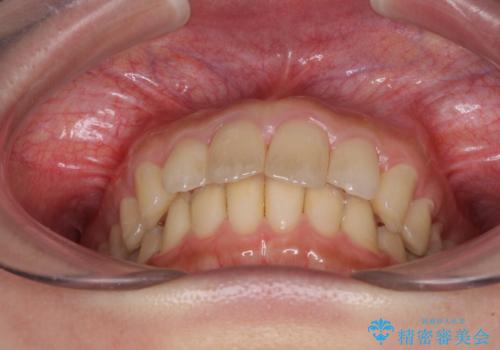

就職前にきれいな歯並びにしたい 大学生のインビザライン矯正

- 就職するまでに歯並びをきれいにしたいとのことで来院された患者様です。

前歯の叢生を気にしていましたが、極力突出感を改善できるようにすることとし、インビザラインにて矯正治療を行うこととしました。

改善の期待できない口元の突出感改善を希望されたため、いたずらに治療期間が延びましたが、きっちりと仕上がりました。